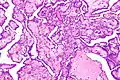

Cancer cells have distinguishing histological features visible under the microscope. The nucleus is often large and irregular, and the cytoplasm may also display abnormalities.[3]

Nucleus

The shape, size, protein composition, and texture of the nucleus are often altered in malignant cells. The nucleus may acquire grooves, folds or indentations, chromatin may aggregate or disperse, and the nucleolus can become enlarged. In normal cells, the nucleus is often round or solid in shape, but in cancer cells the outline is often irregular. Different combinations of abnormalities are characteristic of different cancer types, to the extent that nuclear appearance can be used as a marker in cancer diagnostics and staging.[4]